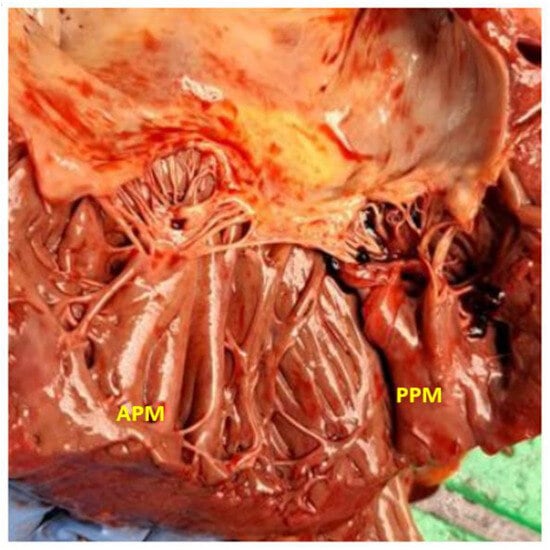

2. Anatomy